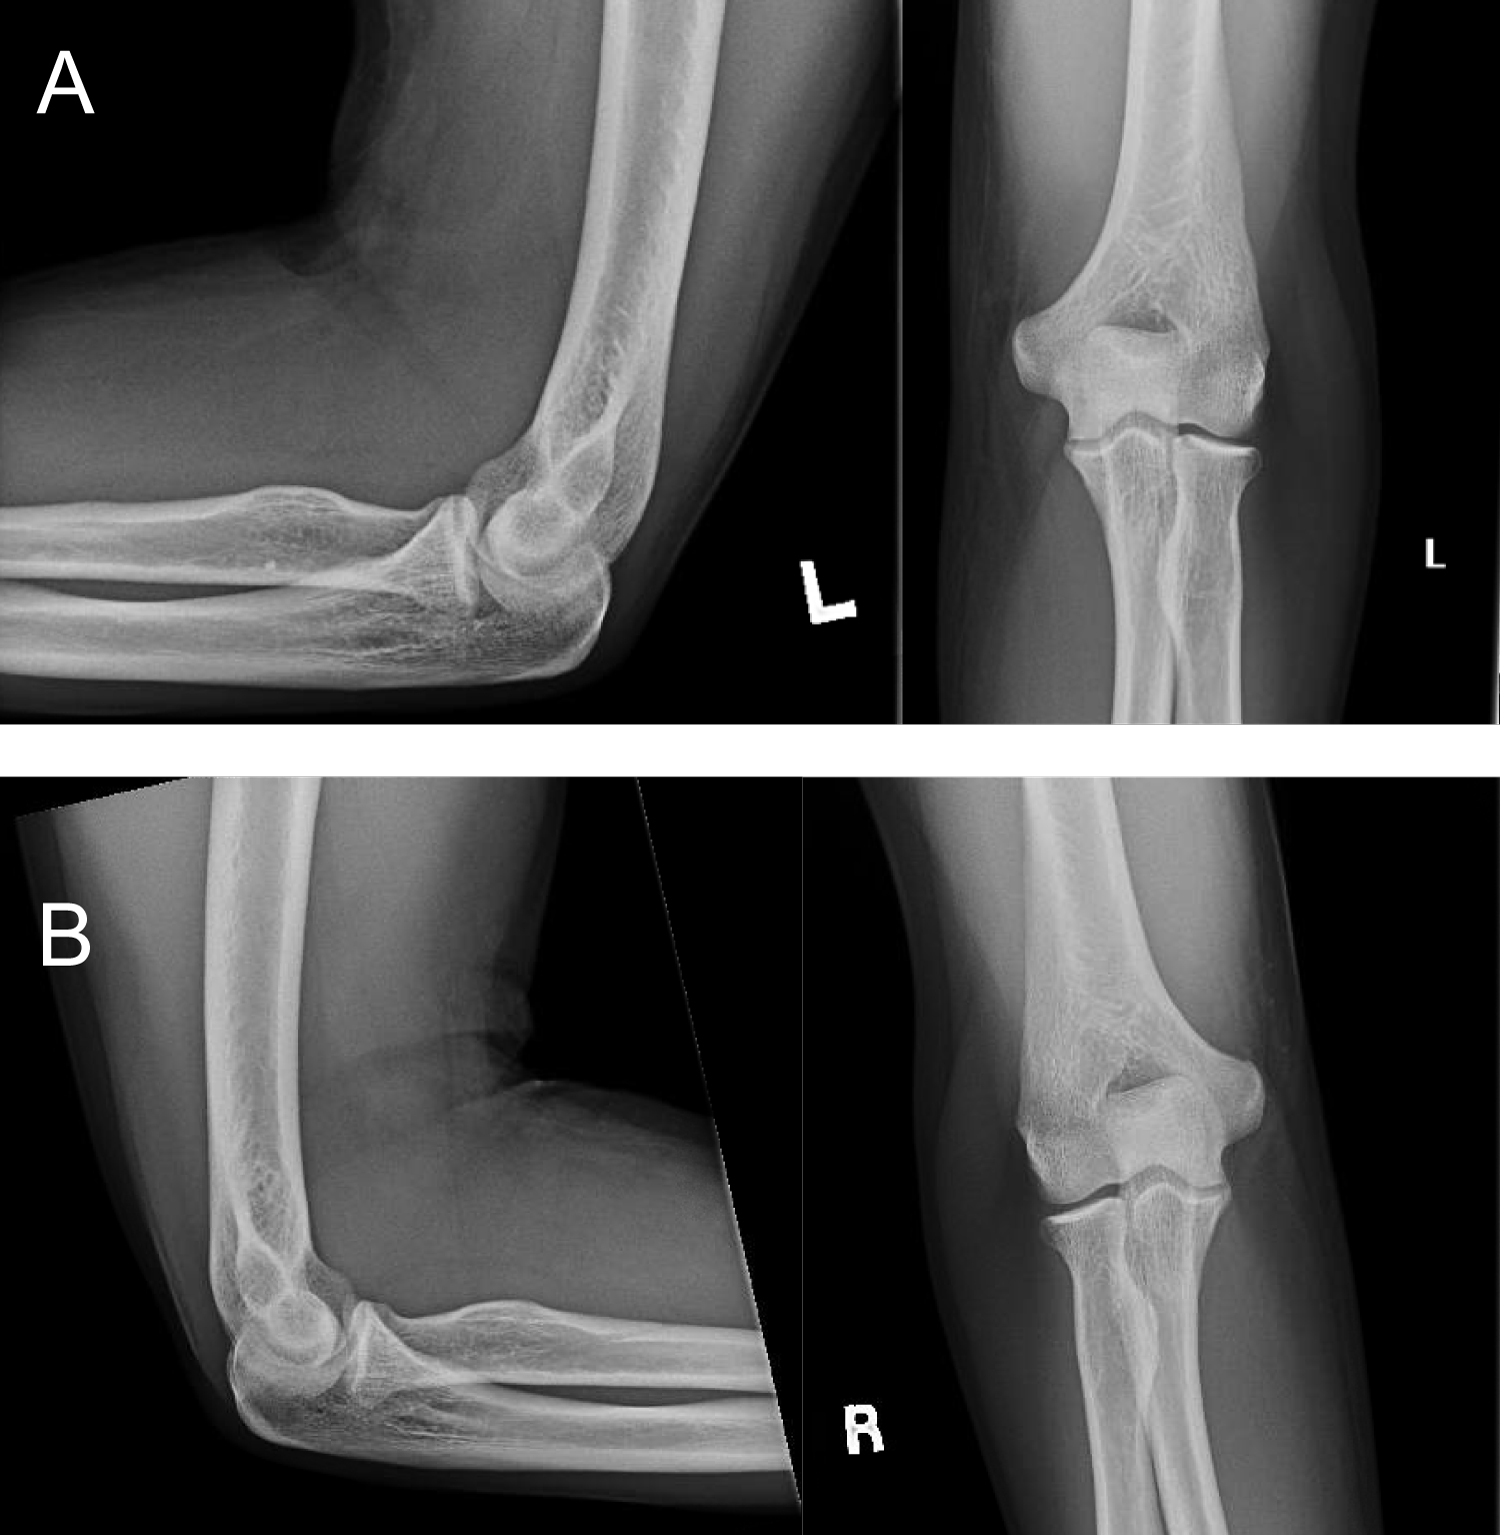

Plain radiographs of both elbows were obtained which did not demonstrate any acute osseous abnormalities (Figure 1A and Figure 1B). The patient underwent bilateral elbow Magnetic Resonance Imaging (MRI) which revealed bilateral full-thickness rupture of the distal biceps tendon with 5.9 cm retraction on the left and 1.4 cm retraction on the right (Figure 2A and Figure 2B).

Figure 1: Figure 1A and Figure 1B represent AP, lateral, and oblique X-rays of the left and right elbows respectively (A) AP, lateral and oblique X-rays of the left elbow; (B) AP, lateral, and oblique X-rays of the right elbow. View Figure 1